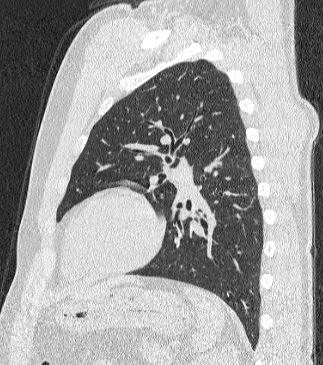

Компьютерная томография бронхов представляет собой виртуальную бронхоскопию, которая позволяет получить точную и достоверную информацию о состоянии трахеи, бронхов, а также оценить структуру легочной ткани, кровеносных сосудов, органов средостения. При обычной бронхоскопии эндоскопический зонд вводится внутрь через дыхательные пути и производится осмотр слизистой трахеи и бронхов, поэтому процедура относится к инвазивным и часто проводится под наркозом.

На основе данных, полученных при сканировании, аппарат создает наглядную 3D модель бронхиального дерева с высочайшей точностью и достоверностью, которая позволяет просматривать интересующие анатомические структуры в разных плоскостях. Метод обладает высокой точностью и дает возможность исследовать мелкие бронхи и бронхиолы, которые из-за узкого просвета бывает невозможно осмотреть при помощи эндоскопической бронхоскопии (возможности метода ограничены размером зонда).